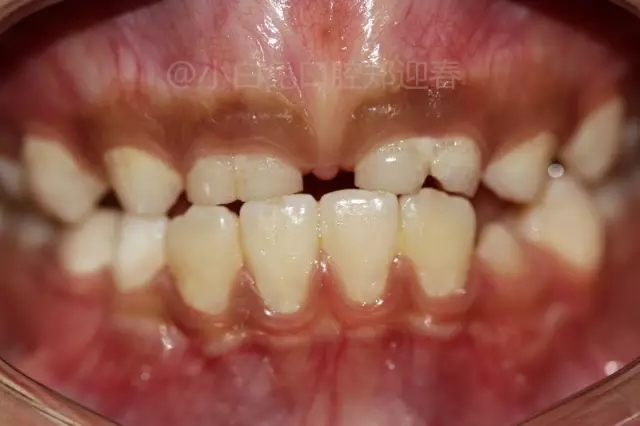

病例分享//一例罕見上頜多牙融合病例

患兒,10歲,因上前牙未替換來診,查體:輕度反合,51和52、61和62均融合,且存在間隙約4mm,全面曲面斷層片顯示:11、21未萌,52、51、61、62牙根均有不同程度的生理性吸收。